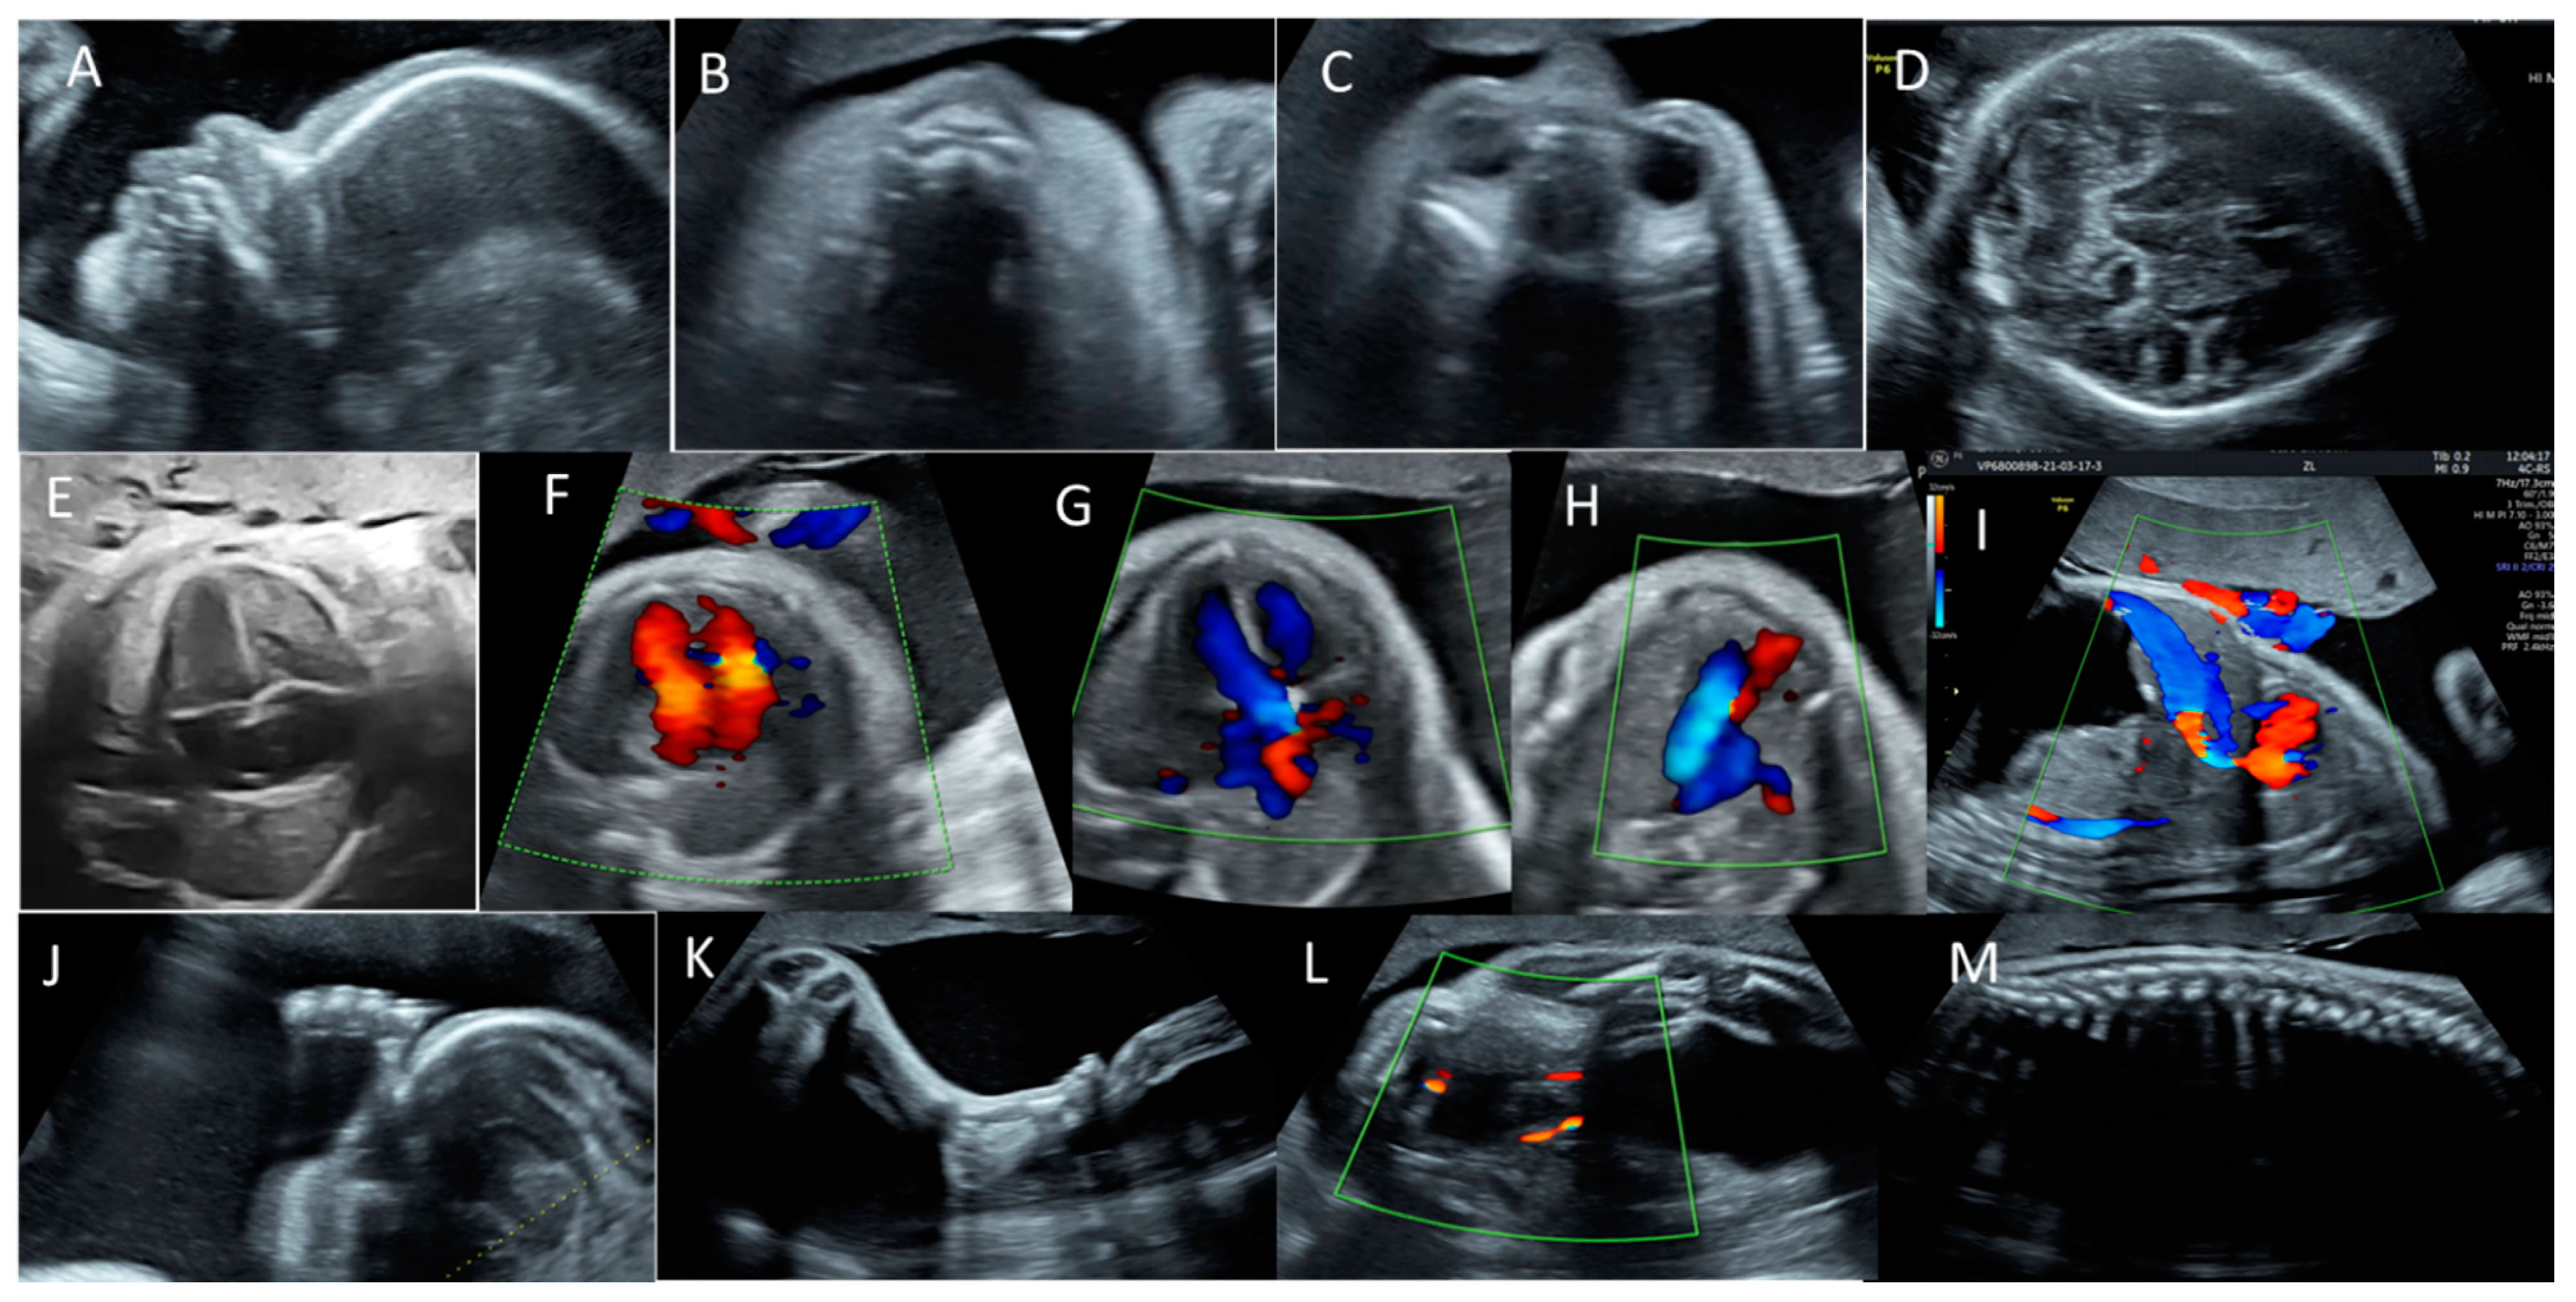

2. Case Report